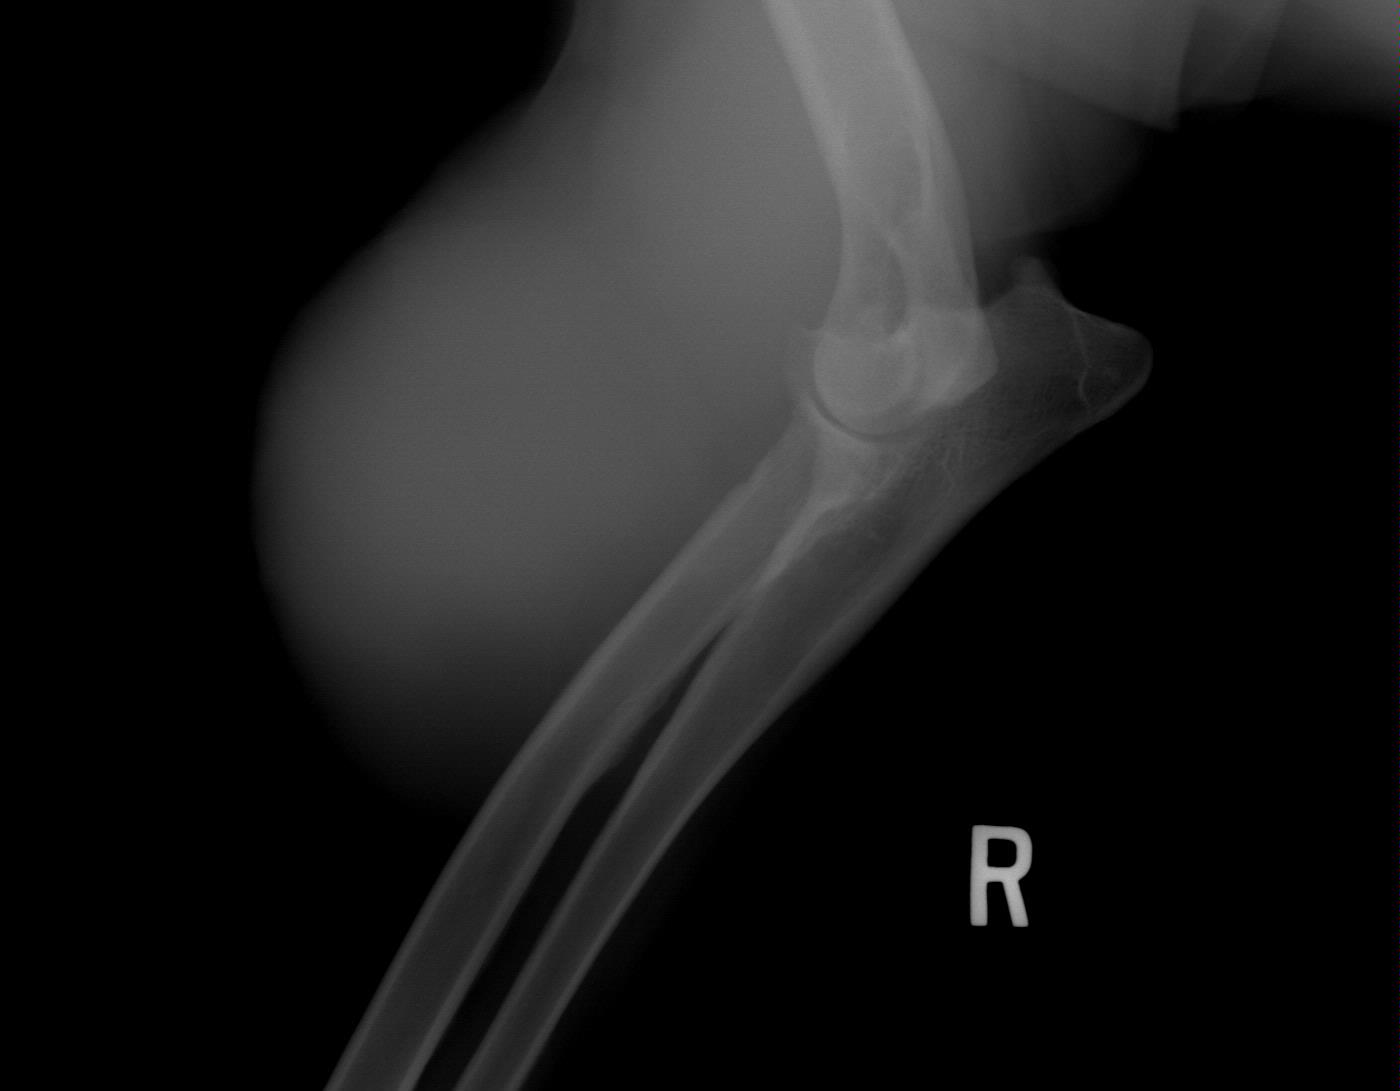

August 1, 2008 - X-rays taken at AMVC in Audubon, IA by Dr. Kristin Longfellow. She was not sedated for the x-rays. She was in slight discomfort in the area of the elbow if pressure was applied, at times seeing her trying to put weight on her toes, she was not in distress, but stiff and sore. We increased her metacam up to her weight limit.

August 4, 2008, Zoey was miserable, reluctance to go down two steps; favoring her front leg; licking it; swelling around elbow; very limited movement, etc. The swelling on the right elbow is not warm, nor cold to touch (unchanged). The swelling is hard/solid. Zoey was sleeping on her blanket (orthoped bed) on the floor without attempting to get on the bed with us at night. Zoey's eyes said she was miserable even though she was trying not to show it. The right leg is clearly marked on the xrays. She was conscious and not sedated for the xrays.

Zoey seen August 1, 2008 by Dr. Kristin Longfellow

due to limping and swelling of the front right forearm/elbow/shoulder area.

X-rays below.

On July 3, 2008, after Zoey finished her pig ear she was chasing her tail and caught the corner of the wall and never recovered from her injuries.The xray was taken 2/13/09

The following xrays were taken August 2008.